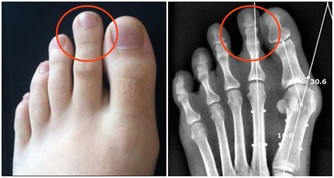

「環軸關節」在哪裡?有憂鬱傾向的人這會痛。 「環軸關節」是指頭部和頸部接合處的關節,

位在第一頸椎和第二頸椎之間;其反射區在腳姆趾趾腹上方1/3的橫切線。